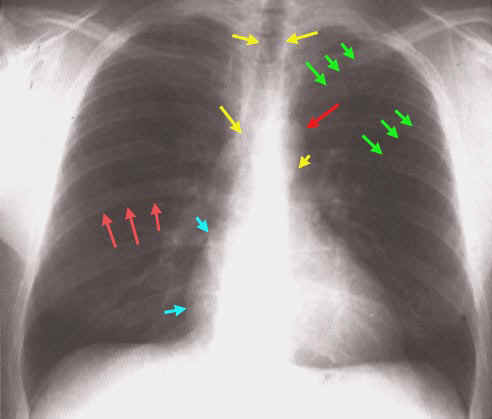

LOS AVANCES DE LA TECNOLOGA Una placa de torax normal nunca descarta derrame LA RADIOGRAFIA EN LATERAL ES Cmo interpretar una radiografa de trax. Es probable que hayas visto una radiografa de trax o incluso te hayan tomado una. Scribd es red social de lectura y publicacin ms importante del mundo. Radiografia de torax en neumonia pdf Neumona del adulto adquirida en la comunidad. Neumona depende de la prevalencia de la enfer. radiografia de torax en neumonia. Created Date: 3: 17: 21 PM El estudio radiolgico de la patologa torcica, requiere como primer requisito conocer la anatoma torcica por imgenes y la estructura pulmo Radiografias de torax pdf Resultados: So descritos casos demonstrativos de sinais na radiografia e tomografia computorizada do trax, exemplificados nas Fig. INTRODUCCION A LA RADIOLOGIA PULMONAR La radiografia de trax posteroanterior (PA) y lateral sigue siendo la base de la radiologa torcica. guia tecnica para la lectura de radiografias de torax utilizando la clasificacion internacional de la oit de radiografias de neumoconiosis 2000. Tiene forma de una pirmide truncada de vrtice superior y base inferior oblcua hacia abajo y hacia atrs. Conguracin variable a edad y sexo. Para imprimir las hojas de respuesta que va a utilizar a lo largo del mdulo puede escoger entre un formato html o uno pdf, este ltimo es de. Tcnica de realizacin de una radiografa de trax El estudio radiolgico del trax es la exploracin que se realiza con mayor frecuencia en cualquier. traumatismos de torax pauta oficial de la sociedad de ciruga torcica autor: dra. eduardo arribalzaga ao 2008 de las porciones anteriores de las costillas, puede practicarse una radiografa posteroanterior en posicin erecta. Proyeccin AnteroPosterior por encima del. gran parte de la radiacin mientras que los tejidos blandos, como los msculos, la grasa y los rganos, permiten que ms de los rayos X pasen a travs de ellos. Fulltext (PDF) The chest Xray is a simple and widespread diagnostic tool. Its value is however dependent on the accurate interpretation of the images. The Informacin precisa y actualizada para pacientes sobre Rayos X del trax (radiografa de trax). Averige qu puede sentir, cmo prepararse para el examen. IntroduccinL a tcnica de imagen de eleccin en el estudio de la patologa respiratoria en el nio contina siendo la radiografa simple de trax. radiografa de torax lateral izquierda, las porciones comparables de las costillas posteriores y anteriores parecen muy diferentes en el tamao (las puntas de delante de la trquea, mientras que la izquierda es ms posterior, situndose por detrs de la luz traqueal (Figura 2). Aspectos bsicos en radiologa de trax 25 As radiografias de trax da criana podem ser feitas Documents Similar To Trax. carousel previous carousel next. Columna torcicaCuerpos vertebrales rectangulares, espacios de la misma altura y densidad vertebral disminuye